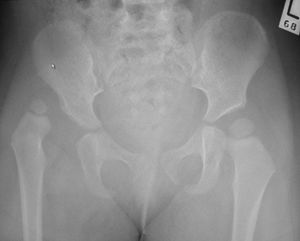

나이가 들어서도 고관절 이형성증이 발생할 수 있다. 고관절 이형성증이 있는 청소년 및 성인은 절뚝거리는 보행, 트렌델렌부르크 징후, 고관절 외전 감소, 고관절 통증 및 일부 경우 고관절 순 파열을 나타낼 수 있다. 투사 방사선 촬영(X-ray)은 고관절 이형성증의 진단을 확인하는 데 사용된다. CT 스캔과 MRI 스캔도 가끔 사용된다.[36][37]

고관절 이형성증 엑스레이 사진도 참고할 수 있다. 골반 X-레이는 고관절 이형성증을 진단하거나 모니터링하거나, 다른 선천성 질환 또는 골종양을 평가하는 데 여전히 자주 사용된다.[45]

골반 X-레이는 고관절 이형성증을 진단하거나 모니터링하거나, 다른 선천성 질환 또는 골종양을 평가하는 데 여전히 자주 사용된다.[45]